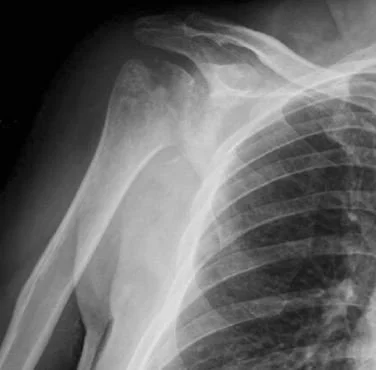

normal shoulder in a 70 y.o.